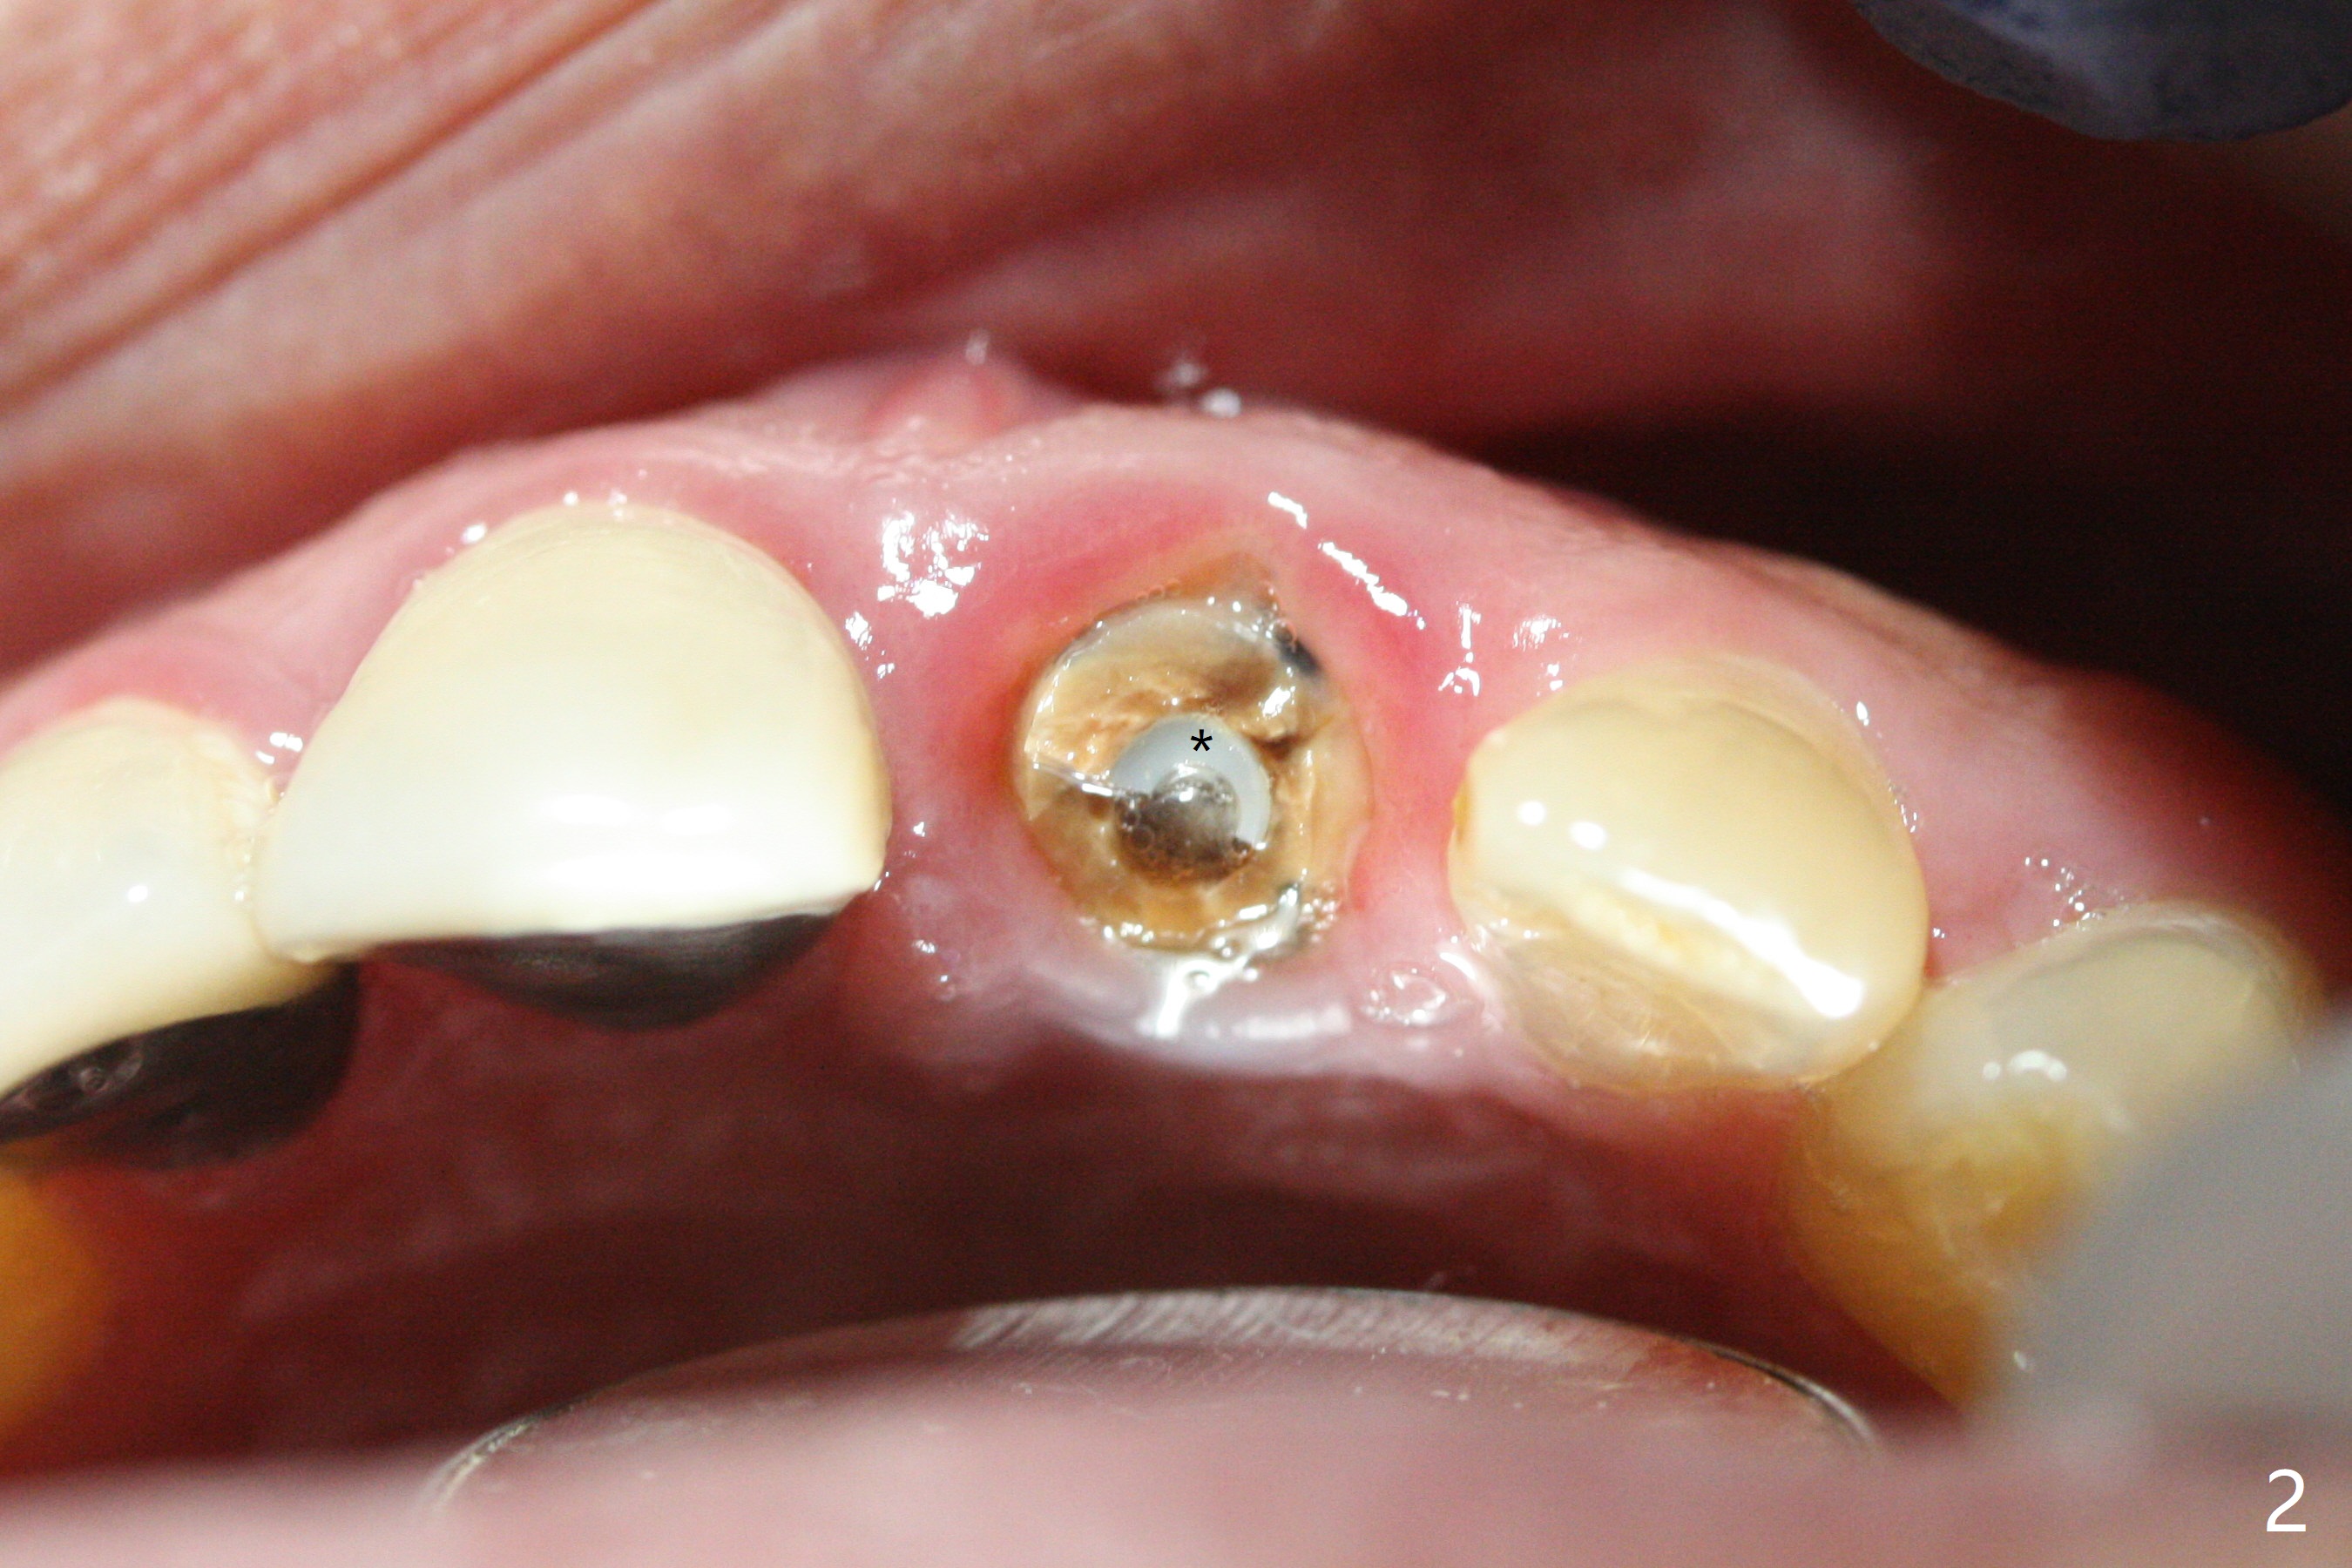

A 58-year-old man fractures the tooth #9 equigingival (Fig.1) and fiber post (Fig.2,3 *). The marginal gingiva is erythematous and edematous (Fig.1 *), suggesting biologic width violation. Redo crown would aggravate the issue. In addition, the mesiobuccal root of the tooth #14 has vertical fracture (Fig.4,5), evidence of heavy mastication. In fact the tooth #13 was also fractured apparently due to heavy occlusion before extraction. It is the best to extract the tooth #9 for implant (Fig.6), or tissue-level (3.5x14 or 17 mm).